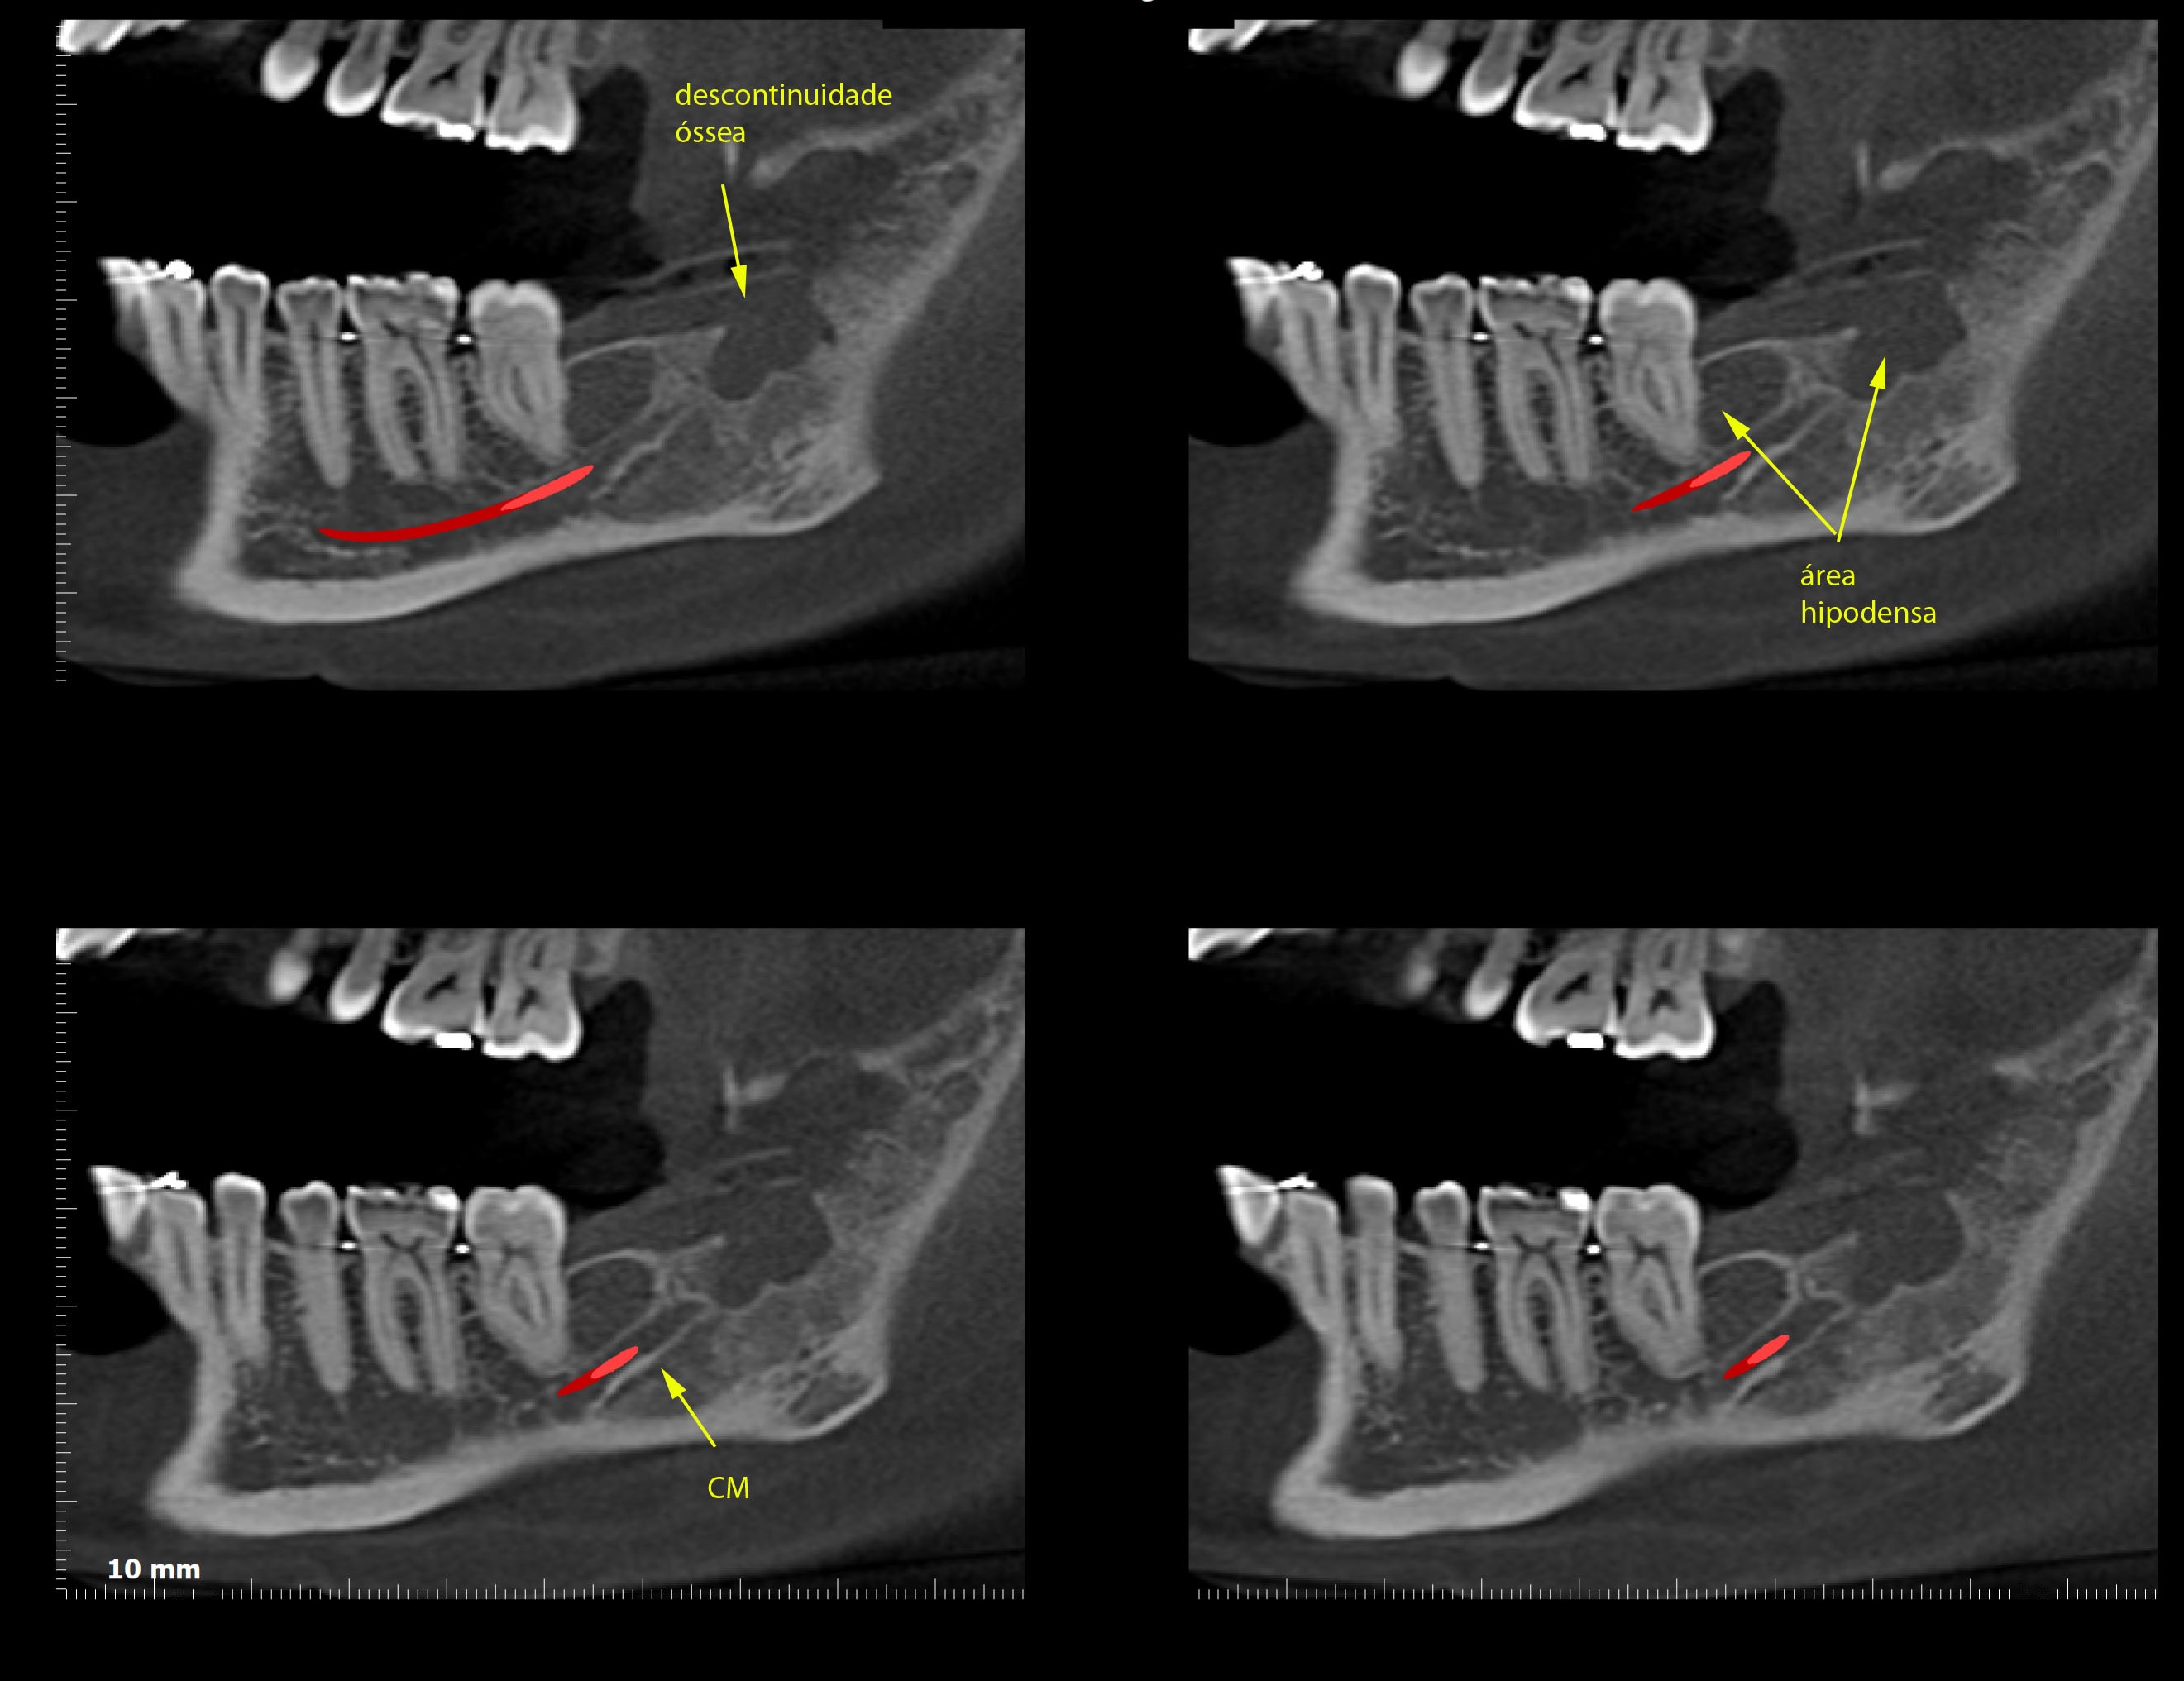

TOMOGRAFIA COMPUTADORIZADA VOLUMÉTRICA CONE BEAM